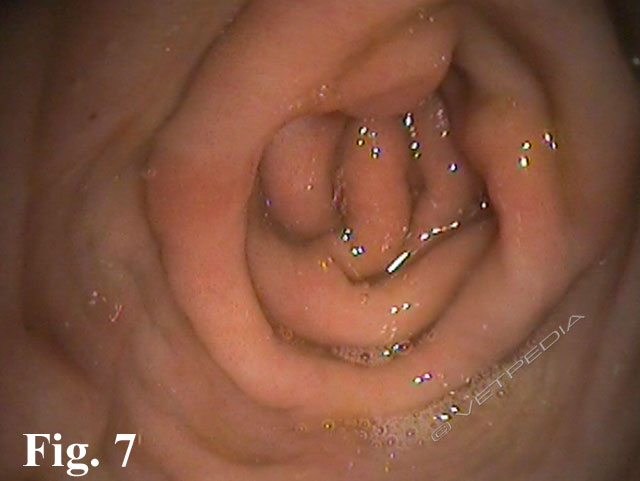

Il criceto può essere affetto da patologie delle tasche guanciali, in particolare costipazioni, prolasso e ascessi. CostipazioneTalvolta il contenuto delle tasche guanciali si impacca e aderisce alle tasche stesse, che il criceto non riesce più a svuotare. Con il tempo il contenuto va in putrefazione. In genere è possibile svuotarle senz...